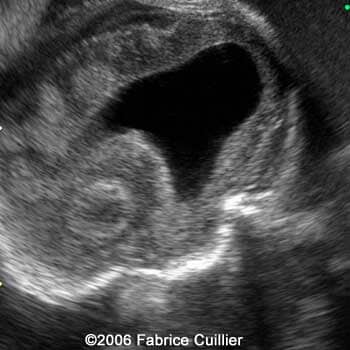

An ultrasound examination was performed in our unit at 30 weeks to evaluate the fetal anatomy. An abdominal scan demonstrated a bilateral hydrocephaly associated with echogenic signs on the brain suggestive of calcifications.

Serial coronal ultrasound view at 30 weeks showing bilateral ventriculomegaly

1